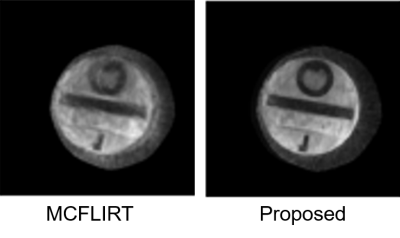

Fig. 2 shows the results of the phantom experiment. Compared with MCFLIRT, our method effectively reduced the blurring caused by the intra-frame motion. Fig. 3 displays the in-vivo reconstruction results, where the proposed method reduced blurring. Fig. 4 shows activation maps calculated from MCFLIRT and the proposed method. MCFLIRT falsely showed activation in the skull due to motion, whereas the proposed method accurately reflected voxels in the motor cortex.

Figure 2. Results of the phantom experiment. In the presence of strong motion, the registration-based method (MCFLIRT) cannot resolve the blurring caused by the inter-shot movement.